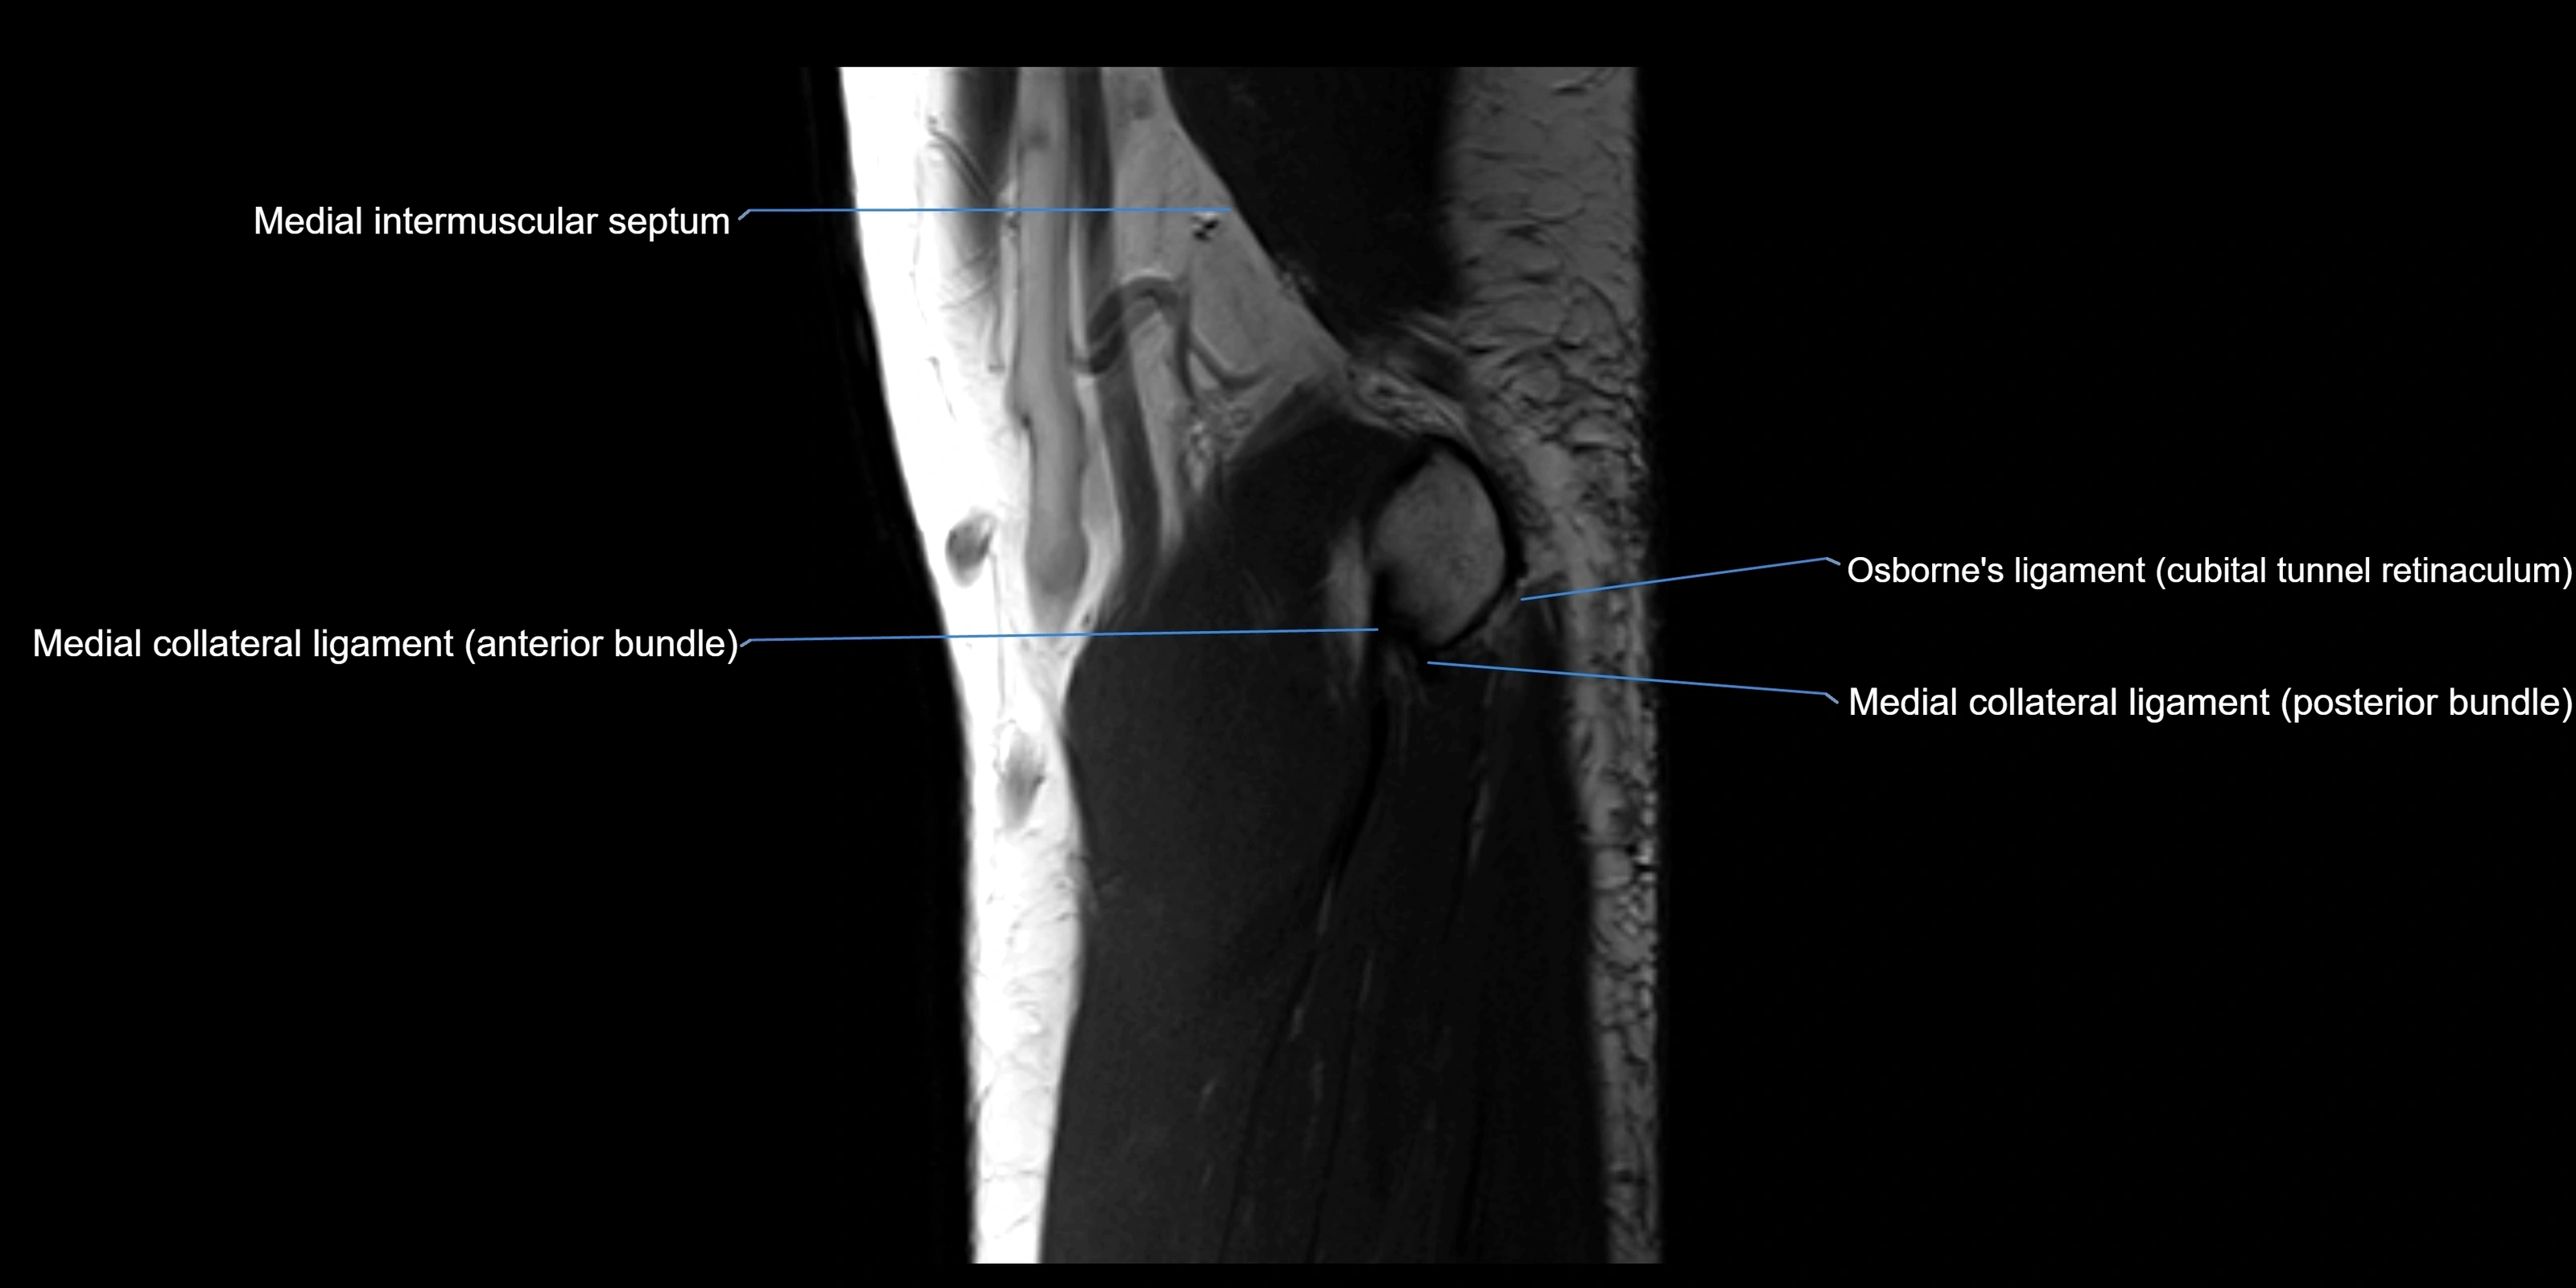

MRI images

image